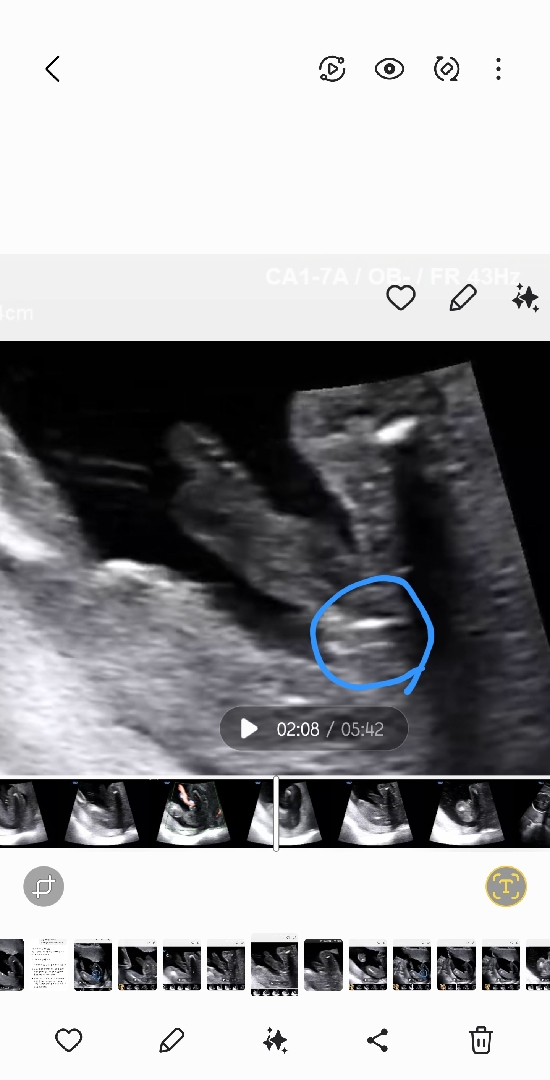

역대급 탯줄.. 18주에도 성별 정확히 모르겠네요

탯줄이 계속 다리사이로 지나가서 정확한성별을 지금까지도 모르겠네요ㅠㅠ 의사선생님도 아들같다곤하는데 막상 초음파 살펴보면 저런식으로 관모양있고.. 탯줄 다리사이에 안빠지려나요

병원에선 아들일거같다곤하는데 다리사이에 계속 탯줄이 지나가서요ㅠ 탯줄 없던때는 다리사이에 아무것도 없었거든요